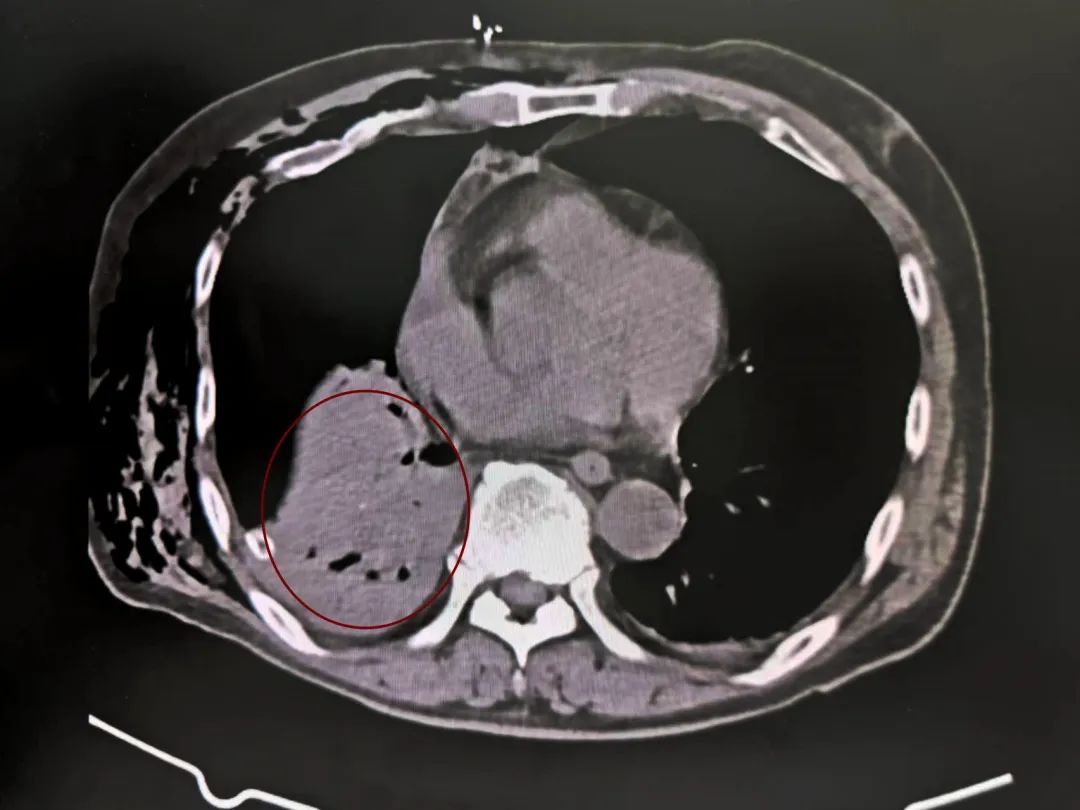

血气肿

系统检查提示:罗叔目前存在车祸后多发伤,头部、胸部、腹部等存在多处外伤,颅脑的挫裂伤,右侧颌面部撕裂伤,右肘关节皮肤裂伤等全身多处皮肤擦伤。外表的伤口已经足够狰狞,而在罗叔的身体内部存在更严重的情况:闭合性颅脑损伤、呼吸衰竭、右侧6根肋骨骨折伴血气胸和皮下气肿、代谢性酸中毒、呼吸性碱中毒,还有肝、肺挫伤等脏器损伤。

当天10:12,在发现罗叔右侧液气胸加重,并出现呼吸困难,血氧下降情况时,团队迅速响应,进行右侧胸腔闭式引流+右侧皮下气肿引流。

两小时后的血气胸